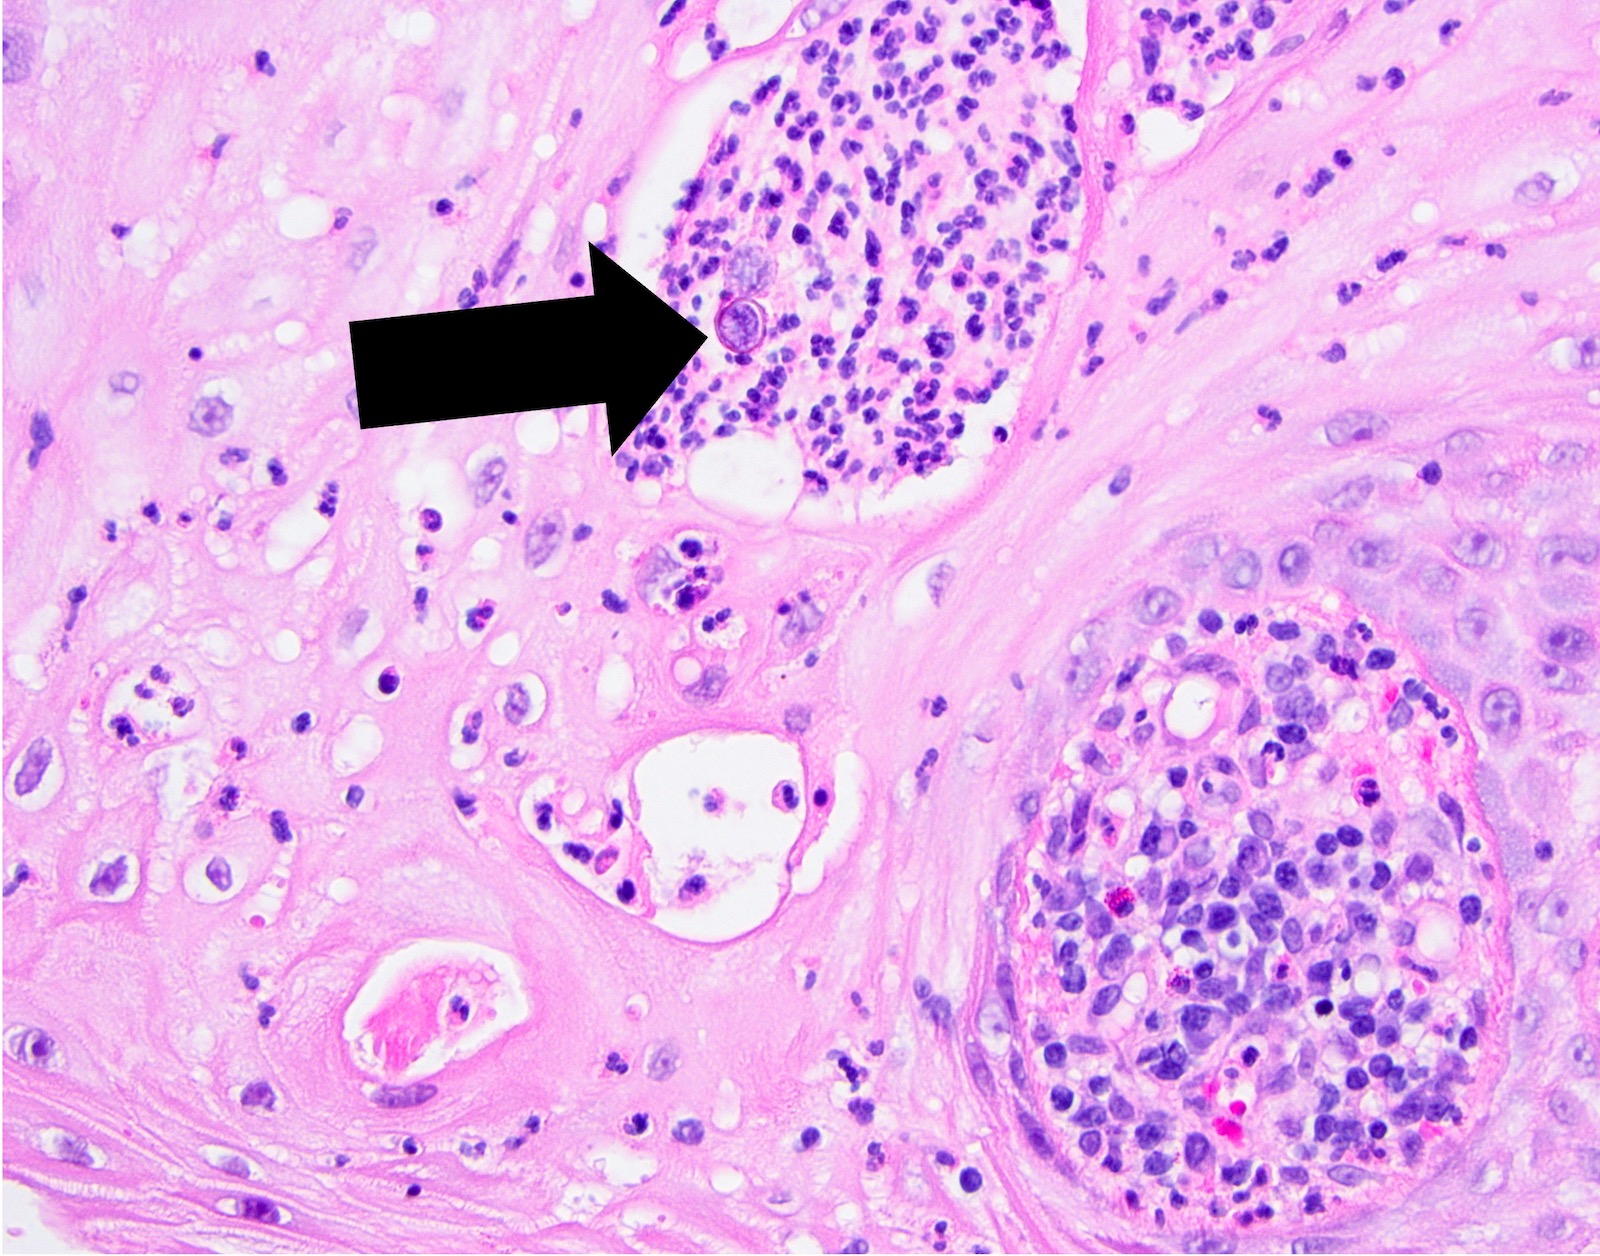

• Prominent leukocytic exocytosis or extravasated red blood cells should alert the pathologist to look for infection (candidiasis, blastomycosis, etc.) or granulomatosis with polyangiitis (Am J Dermatopathol 2011;33:112)

PEH in blastomycosis PEH in blastomycosis

PEH in blastomycosis

Practice question #3

The above biopsy was taken from a patient with a large, indurated ulceration on the tongue. What is the diagnosis?

1. Blastomycosis with pseudoepitheliomatous hyperplasia

2. Granulomatosis with polyangiitis

3. Pyogenic granuloma

4. Squamous cell carcinoma

Practice answer #3

A. Blastomycosis with pseudoepitheliomatous hyperplasia. Blastomycosis is one of the conditions that characteristically shows pseudoepitheliomatous hyperplasia (PEH) in which the epithelium is thickened and forms elongated and anastomosing rete ridges. Answer D is incorrect because although blastomycosis has often been misdiagnosed as squamous cell carcinoma (SCC) due to this prominent PEH, neutrophilic abscesses throughout the epithelium should prompt the pathologist into getting infectious stains, such as the GMS shown above. The GMS stain highlights the thick walled blastomycosis organisms, which show broad based budding. SCC is a common pitfall in the diagnosis of blastomycosis but is incorrect because fungal stains are negative for deep organisms in SCC. Answer B is incorrect because granulomatosis with polyangiitis (GPA) also demonstrates dense inflammation and PEH; however, GPA has evidence of vasculitis and a lack of deep fungal organisms. Answer C is incorrect because pyogenic granulomas can also show dense inflammation and some degree of PEH; however, the epithelium is often not this prolific and microorganisms would not be present on GMS staining.